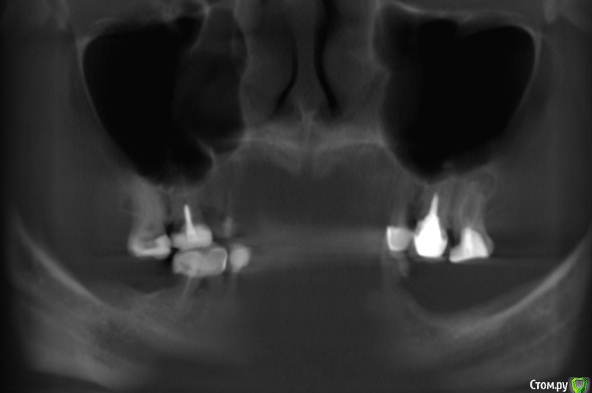

Clearr Опубликовано 8 июля, 2015 Поделиться Опубликовано 8 июля, 2015 Добрый день. Прошу вашего совета!! Объем имплантации в 10 зубов получается немаленький. На сегодняшний день предлагается 2 плана:1. первоначальное удаление ВСЕХ! (7,6,5 слева вверху, 6,5 справа вверху и 6 снизу) проблемных зубов, пролечивание и только потом операции по костной пластике и лифтингу. Объясняется тем, что наличие очагов воспаление в полости гарантирует плохое приживление костной ткани. Итого: либо единомоментная обширная операция на 2 челюстях , либо 2 года без зубов, но потом счастье. 2. 1. Удаление 3-х зубов наверху слева с одномоментным синуслифтингом и костной пластикой на нижней челюсти также слева. В данном случае рабочей останется правая сторона.2.Через 6 месяцев установка имплантатов -2 или 3 штуки верхняя челюсть слева, 2 штуки нижняя челюсть слева3.Через 3 месяца- протезирование на имплантатах с левой стороны на верх.и ниж. челюстях, левая сторона введена в строй4.Удаление 2-х зубов на верхней челюсти справа с одномоментным синуслифтингом и НТР в области 4-го ( там, где потеряна кость), а также удаление 6-ки внизу справа ( там воспаление)5. через 6 месяцев установка 3-х имплантатов на верхней челюсти справа и 2-х на нижней челюсти справа6.через 3 месяца протезирование на имплантатах с левой стороны верх и низ. Все равно получается очень много и дорого. Действительно ли надо удалять все эти зубы, даже если они не беспокоят? 7ка с кистой - обнозначное удаление или можно пролечить? Ссылка на КТ https://yadi.sk/d/PLaMcjgPhbGor Ссылка на комментарий

Bier Опубликовано 15 июля, 2015 Поделиться Опубликовано 15 июля, 2015 есть "киста" 100% 1 Ссылка на комментарий